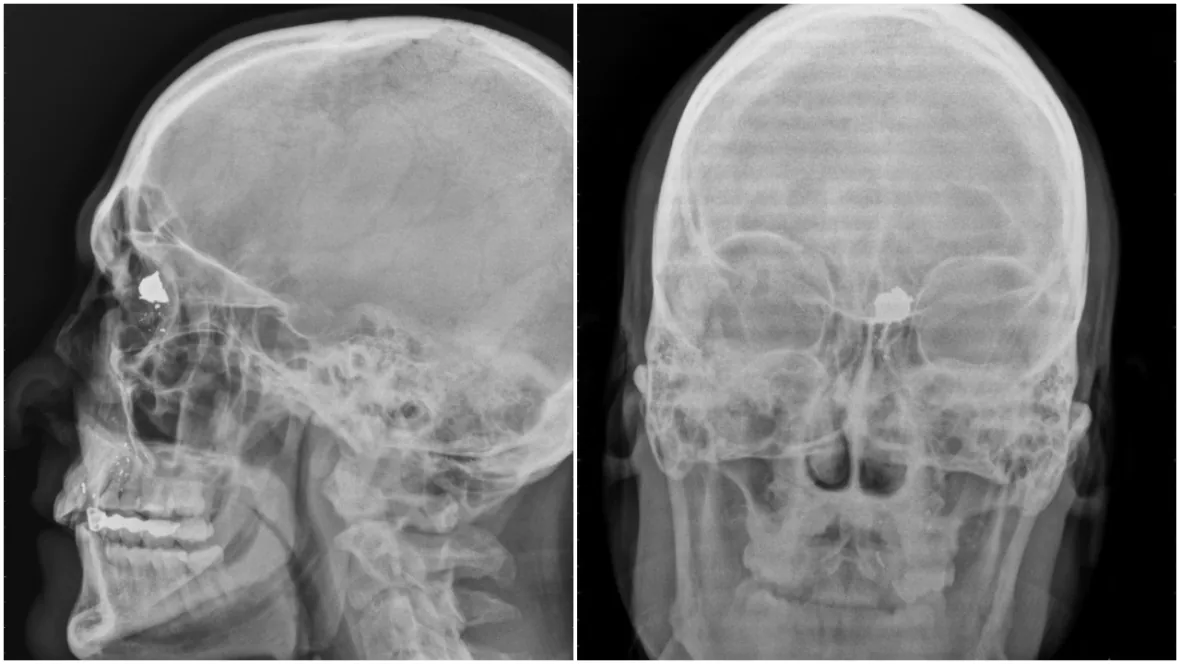

결국 2008년에 라이플로 자살시도했는데 안죽고 또 살음 ㅋㅋ

턱에 대고 소총 방아쇠당겼는데 부비동에 총알 걸려서 생존ㅋㅋ